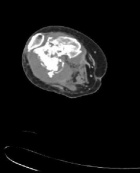

59 year old female complains of knee pain for two months

ESR 112mm/hr

CRP 156 mg/l

WBC 14.6

Zoom image: Radiological image Radiological image.